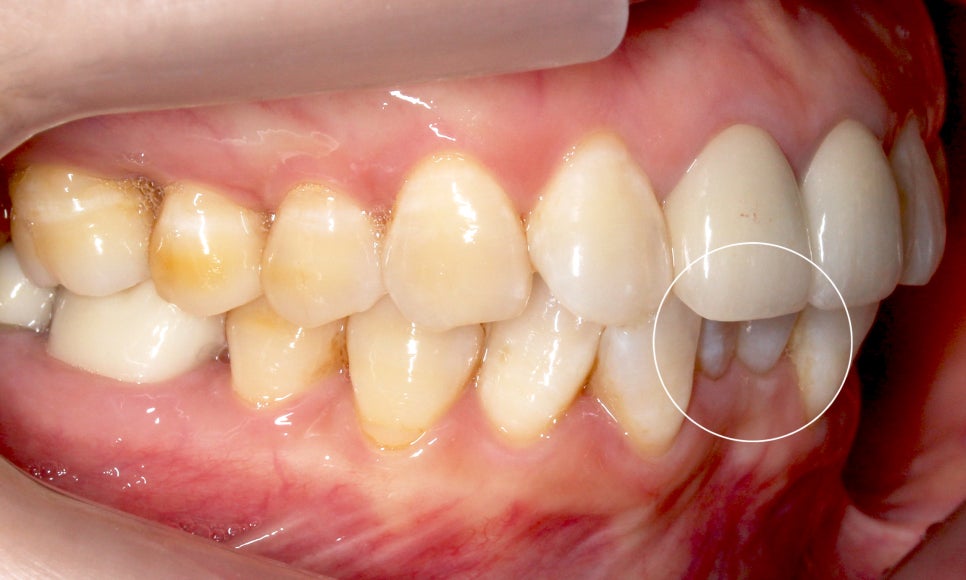

반대쪽도 같은 모습인데요,

이렇게 아랫니가 윗니를 향해

깊숙히 물린다면 아랫니의 절단연에 의해

윗니의 잇몸이 상처를 입을 수 있습니다.

윗니에 가려져서 거의 보이지 않았던

아랫니도 아랫니 부분교정(2D교정)을 통해

정상적인 교합상태로 바뀐 모습입니다~

반대쪽 모습도 과하게 물리는 모습 없이

깔끔하게 교정되었어요 : )